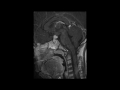

This is a case of Langerhans Cell Histiocytosis, or LCH, of the pituitary gland and infundibulum in a 6-year-old male. The first image is sagittal T1-weighted with some motion degradation. There is thickening of the infundibulum and pituitary gland itself, with classic loss of the typically hyerintense posterior pituitary. The second image is a noncontrast coronal T1 correlate redemonstrating infundibular thickening as well as enlargement of the pituitary gland itself. The third image is with T2 weighting in the coronal plane redemonstrating thickening of the pituitary stalk. The fourth through sixth images are multi planar postcontrast T1-weighted sequences demonstrating avid post contrast enhancement of the markedly enlarged infundibulum and pituitary gland itself. LCH is a reactive clonal disease of the monocyte-macrophage system, and may affect almost any organ system. LCH CNS involvement may fall into one of several forms such as: osseous lesions with or without soft tissue components, intra-cranial extra-axial lesions, such as in the hypothalamic-pituitary region, meninges, or circumventricular organs, intracranial intra-axial lesions and cerebral atrophy. Langerhans cell histiocytosis is the most common cause of infundibular thickening in childhood. Diabetes insipidus is the typical clinical presentation of hypothalamic-pituitary involvement.